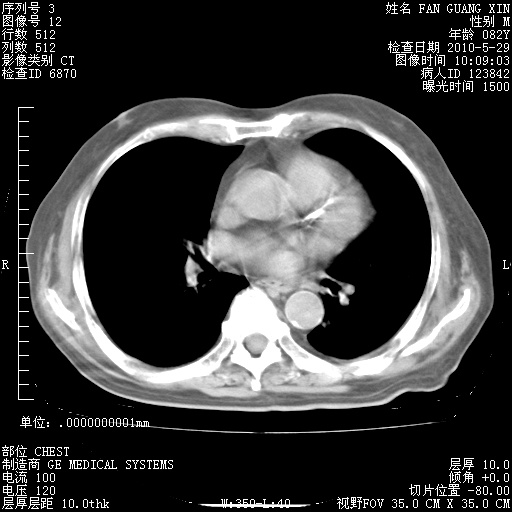

还需要哪些辅助检查?我们医院排除真菌感染没有任何检验方法,胸片好像能够排除肺部真菌感染。